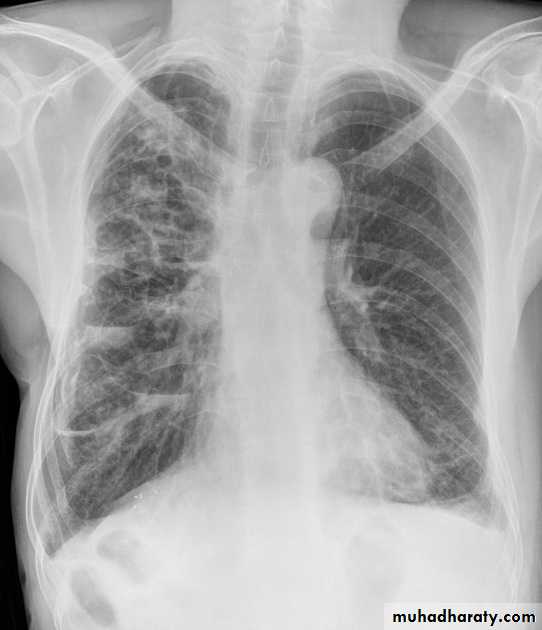

Pulmonary metastases are common and the result of metastatic spread to the lungs from a variety of tumors and can spread via blood or lymphatics.1.Cannonball metastases refer to large well circumscribed, round multiple opacities like cannonballs

2.lymphangitis carcinomatosis , is the term given to tumor spread through the lymphatics of the lung , and is most commonly seen secondary to adenocarcinoma Unfortunately up to a quarter of patients with subsequently established lymphangitic carcinomatosis have normal chest x-rays . When abnormal the most common finding is of a reticulonodular pattern, with thickening of the interlobular septae which may resemble Kerley B lines + /- pleural effusion .

3.innumerable small metastases (miliary pattern).